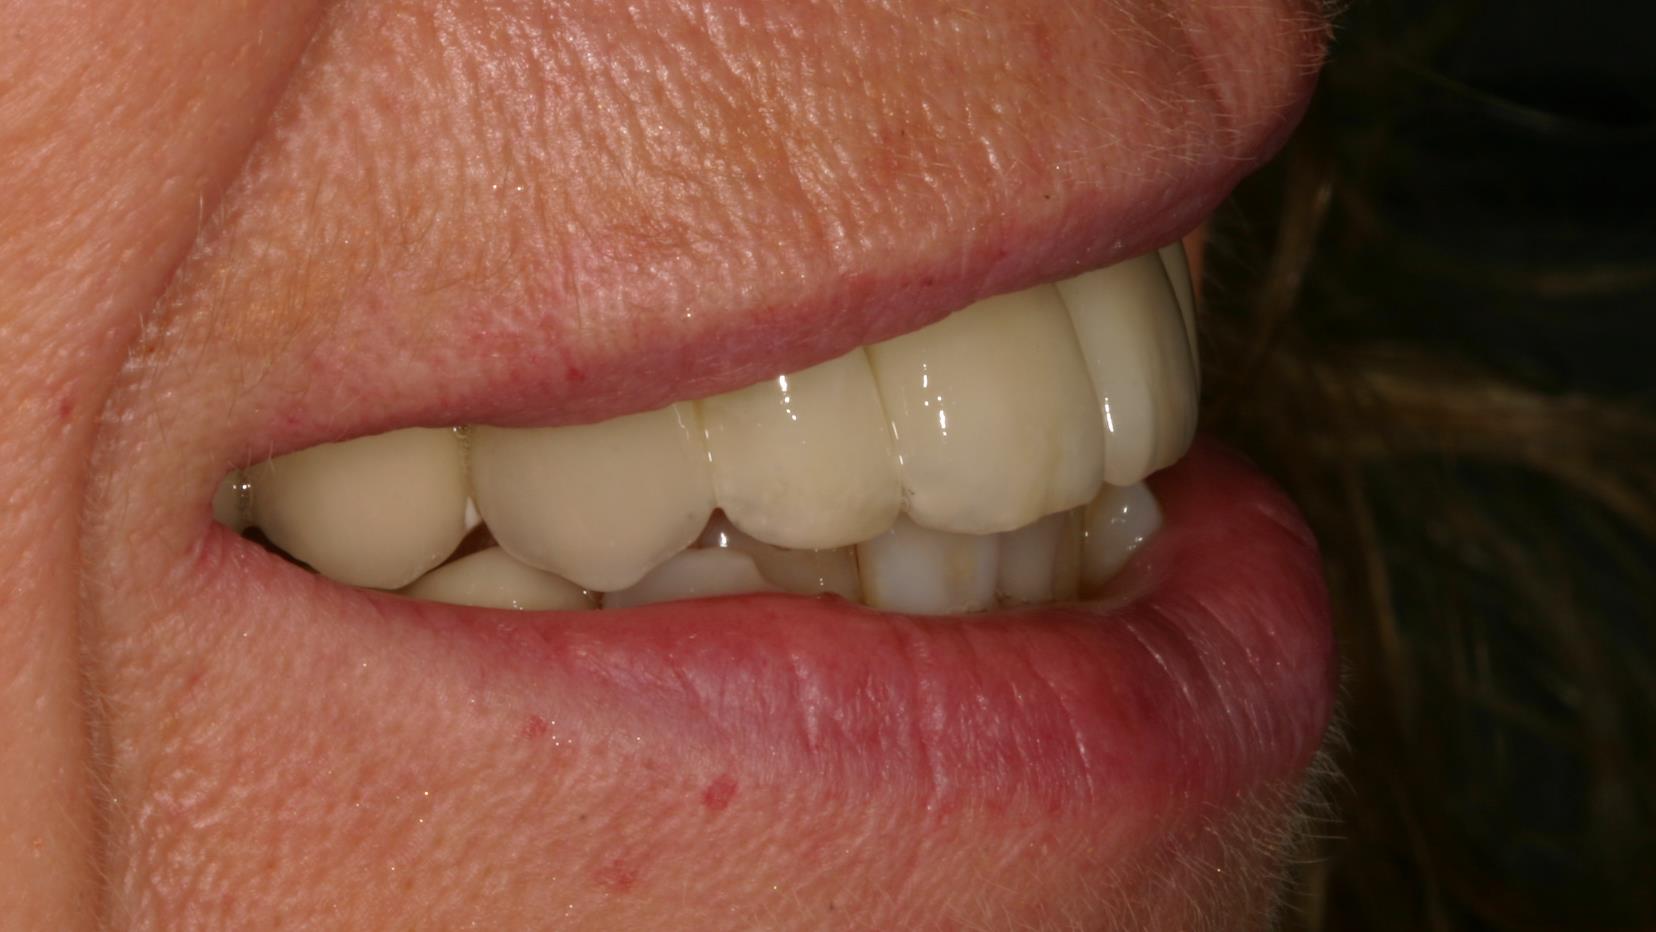

Wenn mehrere Zähne im Frontzahnbereich fehlen, kann man die Lücke durch eine Brücke schließen. Meistens ist dann auch schon der Kieferkamm zurückgeschwunden. Dadurch wirken die Brückenglieder länger. Auch die Zahnfleischpapille fehlt. Hier haben wir sie mit rosa Keramik nachgebildet, um „dunkle Löcher“ zwischen den Zähnen zu vermeiden und die Zähne nicht unnatürlich breit und lang erscheinen zu lassen.